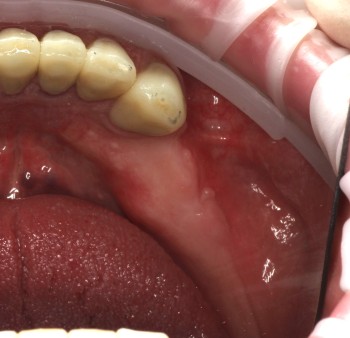

Ястребов Даниил Александрович: портфолио (1)